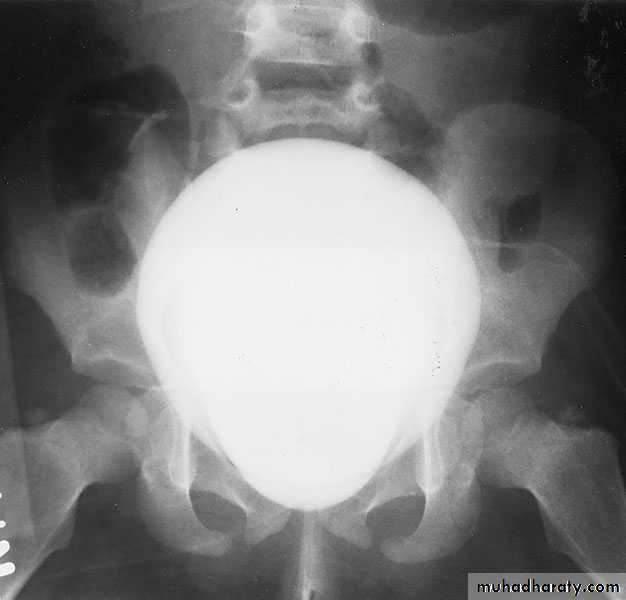

CYSTOURETHROGRAPHY

Contrast-enhanced imaging of the lower urinary tract provides valuable information on the function and anatomy of the bladder and urethraVoiding ( micturating) Cystourethrography (MCUG): looking for vesicoreteric reflux